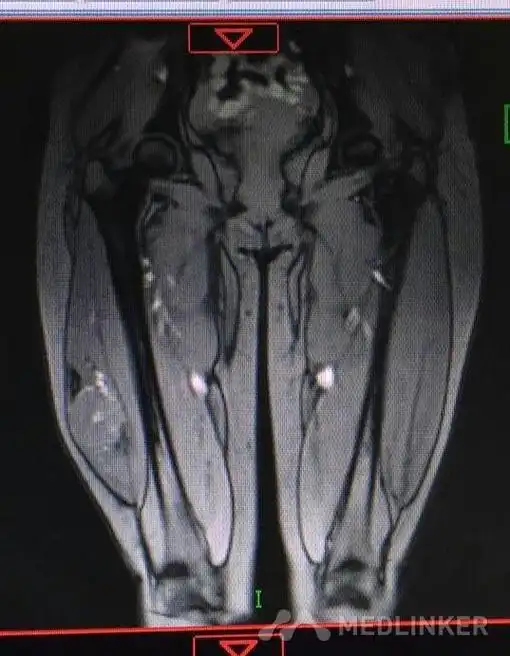

随访 讨论腺泡状软组织肉瘤好发于青春期女性,多位于四肢深部肌肉或